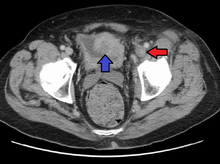

Phlegmasia cerulea dolens (literally: painful blue edema) is an uncommon severe form of deep venous thrombosis which results from extensive thrombotic occlusion (blockage by a thrombus) of the major and the collateral veins of an extremity.[1][2] It is characterized by sudden severe pain, swelling, cyanosis and edema of the affected limb. There is a high risk of massive pulmonary embolism, even under anticoagulation. Foot gangrene may also occur. An underlying malignancy is found in 50% of cases. Usually, it occurs in those afflicted by a life-threatening illness.[1]